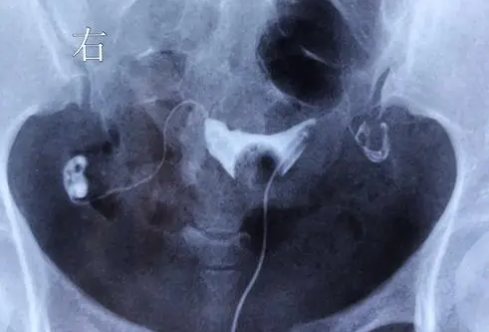

輸卵管檢查是通過特定的醫(yī)療設(shè)備對女性生殖器官進(jìn)行內(nèi)窺鏡檢測和造影術(shù)來確定是否存在輸卵管問題。這個過程可以通過腹腔鏡、盆腔鏡等方式進(jìn)行。